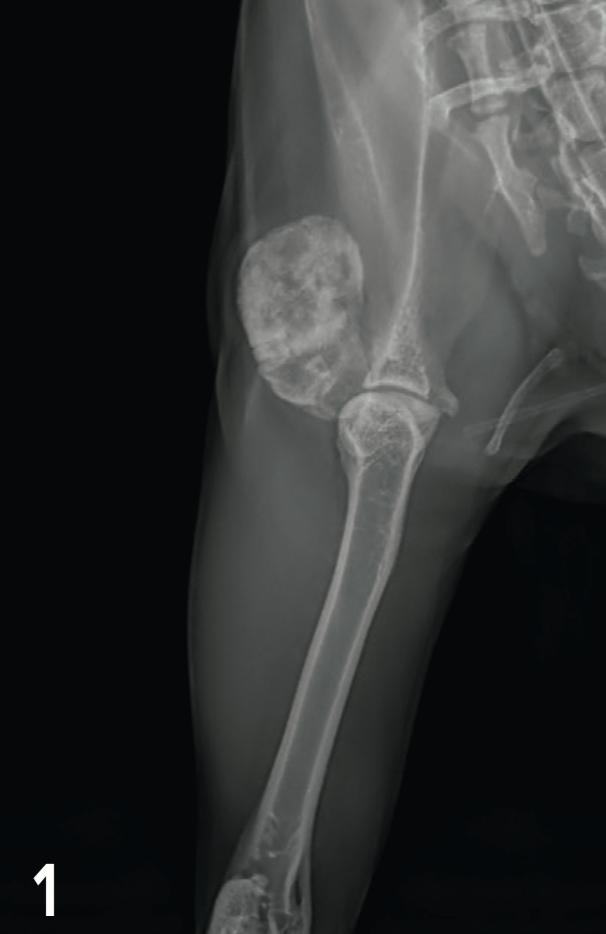

Radiographies des membres thoraciques

Les radiographies du membre thoracique gauche mettent en évidence une lésion d’opacité minérale hétérogène. Cette lésion est bien délimitée, de forme ovoïde et située en face latérale de la scapula gauche, en regard de l’acromion. Aucune tuméfaction des tissus mous périphériques n’est notée (Fig. 1 et 2). Ces images sont compatibles avec un processus tumoral intéressant la scapula gauche dans sa partie distale, l’humérus gauche dans sa partie proximale ou la capsule articulaire scapulo-humérale. Cependant, un phénomène de minéralisation dystrophique ectopique périarticulaire (ostéochondrome, ostéochondromatose...) ne peut être complètement exclu sur la base de ces clichés.

Légendes : Figures 1 et 2 : Radiographies de face et de profil de la scapula gauche à l’admission, mettant en évidence une lésion osseuse bien délimitée en face latérale de la scapula gauche.